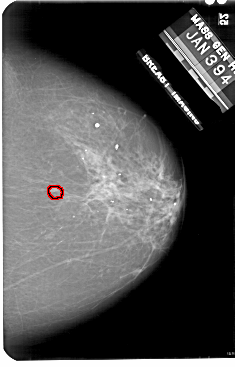

A_1901_1.LEFT_MLO

LEFT_MLO LINES 5491 PIXELS_PER_LINE 3511 BITS_PER_PIXEL 12 RESOLUTION 43.5 NON_OVERLAY

FILE: A_1901_1.RIGHT_MLO.OVERLAY

TOTAL_ABNORMALITIES 1

ABNORMALITY 1

LESION_TYPE MASS SHAPE IRREGULAR MARGINS ILL_DEFINED

ASSESSMENT 4

SUBTLETY 5

PATHOLOGY MALIGNANT

TOTAL_OUTLINES 1

BOUNDARY